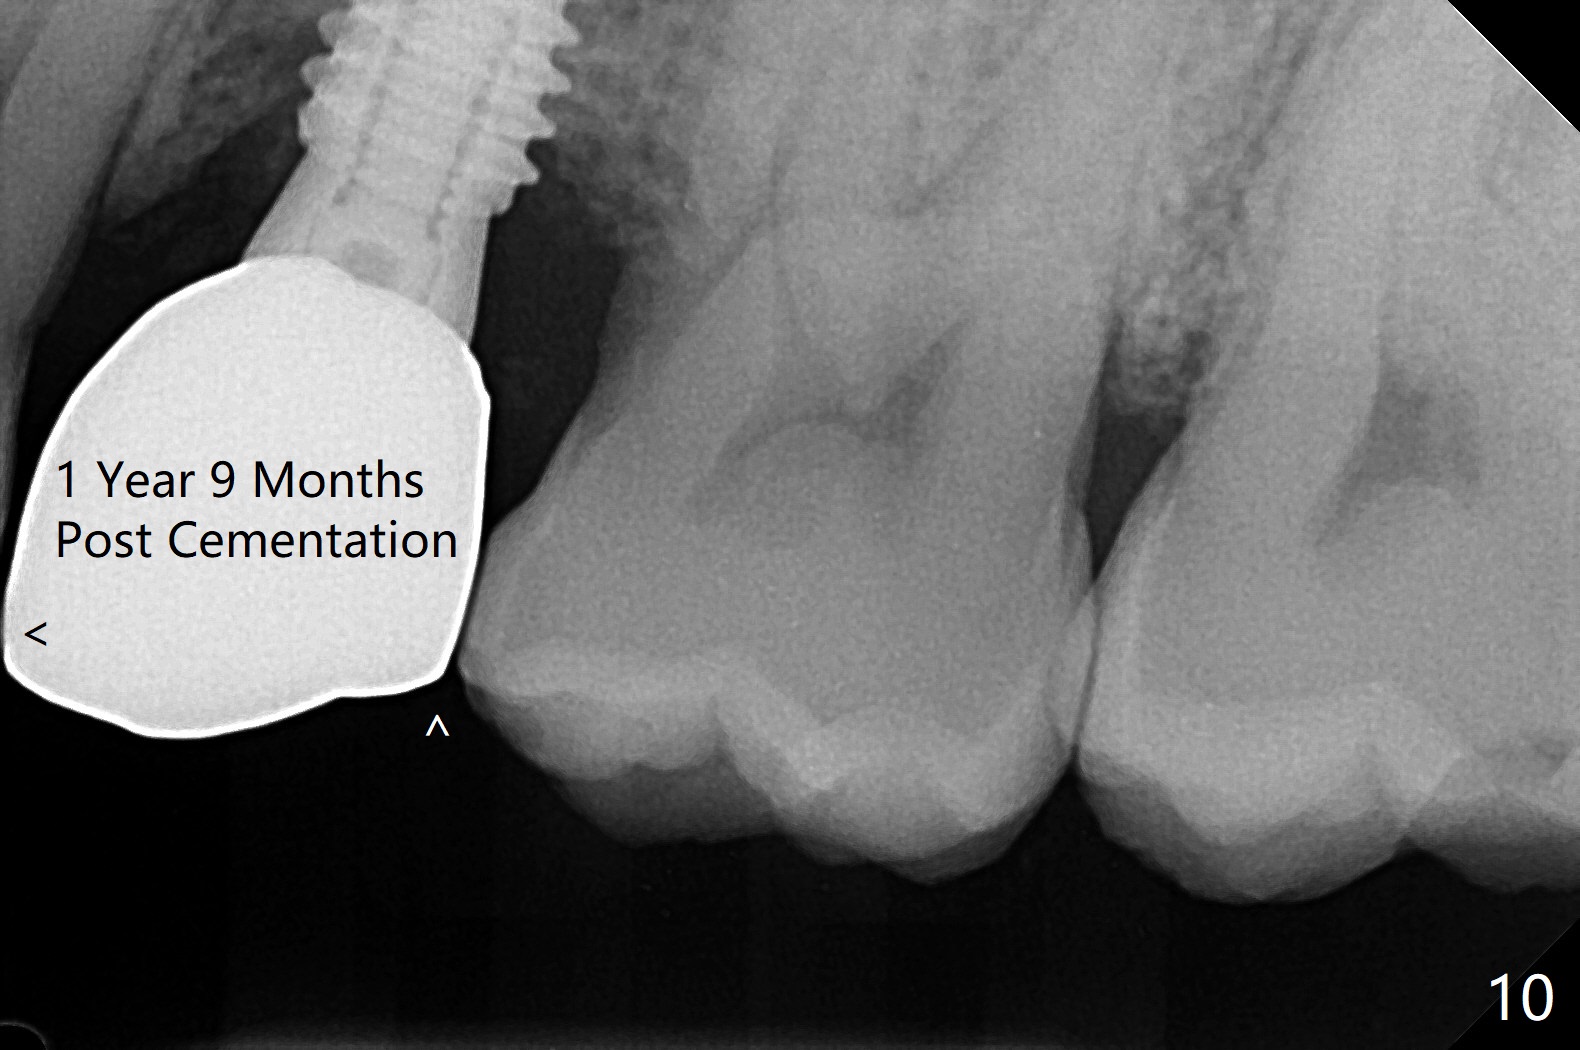

DIO lab refuses fabricating guide because of the large socket and recommends extraction and socket preservation at #13. Due to short apical bone (Fig.5,7), a long dummy implant (3.8x15 mm) is placed with periimplant space immediately post extraction (Fig.1 *). The final implant is larger (4.5x15 mm) with simultaneous sinus lift and periimplant bone graft (Fig.2,6,8 *). To repair the palatal crest defect (Fig.3 *) associated with tooth fracture (Fig.5 white dashed line), the implant is not placed too palatal with sufficient amount of the bone graft (Fig.4,6 *). The native bone (higher in bone density, Fig.9 white arrowheads, as compared to black one (for bone graft)) appears to have grown into the space between implant threads 5.5 months postop. The permanent crown/abutment is loose 1 year 9 months post cementation; after proximal reduction (Fig.10 arrowheads), the abutment is reseated completely. Pick up impression is taken and a healing abutment is placed. A few days later, the crown and abutment (separate) are seated passively; the abutment screw is retightened; the crown is re-cemented. The crown and abutment is removed for residual cement removal (Fig.11). Since there is mild buccal plate atrophy (Fig.11 B), the crown has a buccal lip (Fig.12 B) to prevent food impaction. The lip makes it difficult to remove residual cement intraorally. Therefore an access hole is necessary (Fig.13).